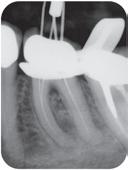

-30% på alle TrollByte Kimera røntgenholdere

Gjelder til 15.11.2024

TrollByte Kimera finnes for alle typer sensorer, fosforplater og film. TrollByte enkel å bruke. Stive, robuste holdere som gir deg full kontroll når du skal ta bilde. Ingen artefakter på bildene fra holderen. Kan autoklaveres. Produsert av miljøvennligere bioplast - enda et viktig miljøtiltak.

Vi hjelper deg å finne riktig. Ring oss på telefon 66892050, på post@td.no eller på LiveChat på www.td.no

Kompakt og stiv holder for enkelt å ta bitewing. 3-pk røde holdere (var tidligere rød/sort). Før 1.499,-

Startsett m/én av hver TrollByte Kimera rød, gul og blå, samt siktering og bittblokk. 3-pk. Ønsker du bare én farge så velg et av settene nedenfor. Før 1.499,-

Stående holder for periapikale opptak. Siktering og bittblokk følger med. 3-pk blå. Før 1.499,-

1.049,3-pk

Periapikal liggende (gul)

Liggende holder for periapikale opptak og bitewing. Siktering og bittblokk følger med. 3-pk gul. Før 1.499,-

For indikatorbilder og sluttbilder. Sett med blå spesial endoholder for stående, og gul spesial endoholder for liggende opptak. Med rød og grønn endobittblokk og siktering. Finnes for alle sensorer, plater og film. Før 1.799,-

Hva betyr TrollByte-nummeret?

Eksempel: 4305/2905. 43=lengden på sensoren, 29=høyden, 05=tykkelse på sensor, målt i millimeter. 4305=mål for gul holder / 2905=mål for rød/blå holder. Mål gjerne din sensor. Vi hjelper deg gjerne!